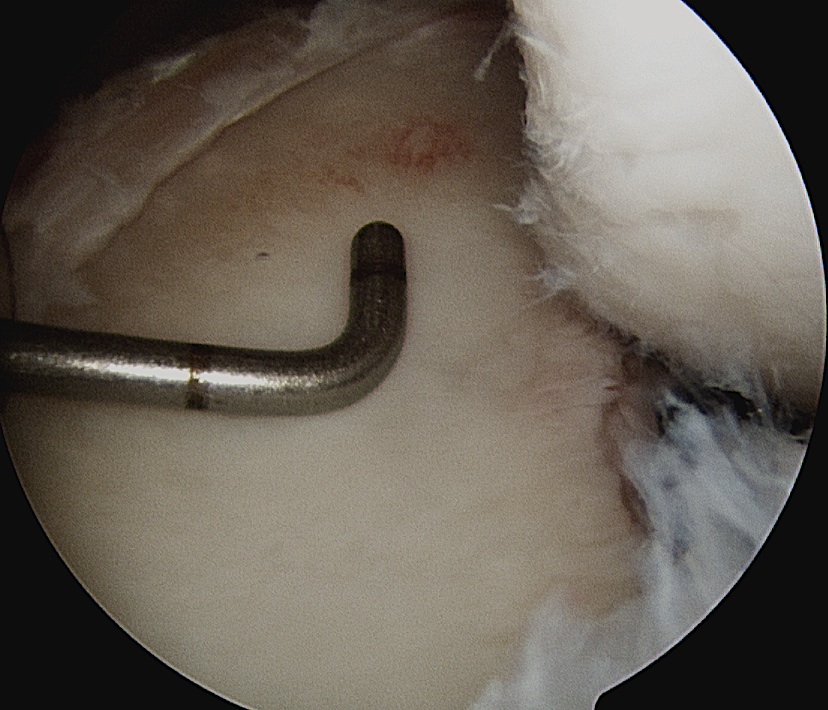

Mobilize anterior labrum

Mobilize labrum

Labral mobiliser / rasp

- labral tear can be obvious, but may have partially healed or healed medially

- change camera to anterosuperior portal for better view

- mobilize until can see subscapularis muscle underneath

- need to be able to advance labrum medially and superiorly for repair

Debride anterior glenoid bone to bleeding bone